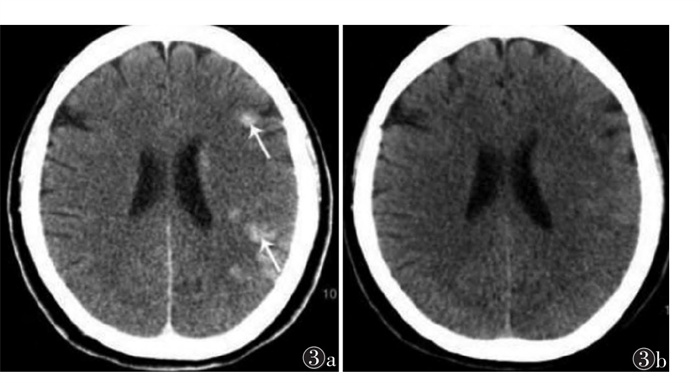

| 注:患者,女,74岁,突发意识不清、言语不能伴右侧肢体活动不能5 h。图 2a为术后即刻颅脑CT,示左侧侧脑室后角内斑片状高密度影(箭头),可见液液平面,CT值约140 HU;图 2b为术后第2天复查CT,示高密度影消失 图 2 Ⅱ型B组急性缺血性脑卒中CT图像 |

| 注:患者,女,62岁,突然言语不能伴右侧肢体活动不能3 h余脑回状对比剂溢出。图 3a为术后即刻颅脑CT,示左侧额顶叶片状高密度影(箭头),CT值约66 HU,周围脑组织无肿胀,邻近脑沟未见变窄;图 3b为术后当天复查CT,示高密度影消失;此例为脑室内对比剂溢出 图 3 Ⅱ型C组急性缺血性脑卒中CT图像 |